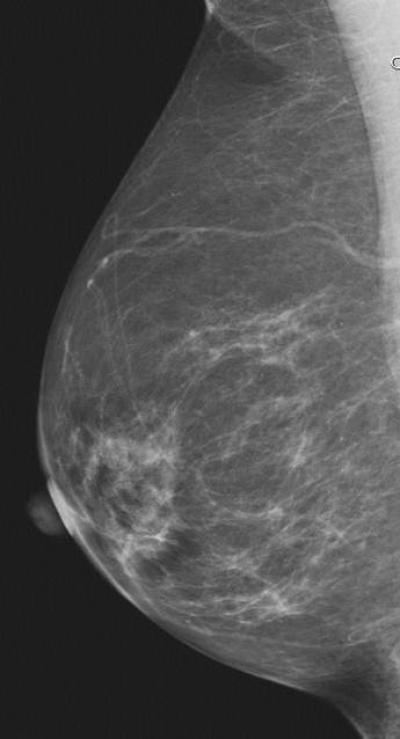

CHICAGO – Automated breast density measurement is predictive of breast cancer risk in younger women, and that risk may be related to the rate at which breast density changes in some women as they age, according to research being presented today at the annual meeting of the Radiological Society of North America (RSNA).

Breast density, as determined by mammography, is already known to be a strong and independent risk factor for breast cancer. The American Cancer Society (ACS) considers women with extremely dense breasts to be at moderately increased risk of cancer and recommends they talk with their doctors about adding magnetic resonance imaging (MRI) screening to their yearly mammograms.

For the new study, Dr. Perry and colleagues compared breast density and cancer risk between younger and older women and analyzed how the risk relates to changes in breast density over time. The study group included 282 breast cancer cases and 317 healthy control participants who underwent full-field digital mammography, with breast density measured separately using an automated volumetric system.

"In general, we refer to breast density as being determined by mammographic appearance, and that has, by and large, in the past been done by visual estimation by the radiologist—in other words, subjective and qualitative," Dr. Perry said. "The automated system we used in the study is an algorithm that can be automatically and easily applied to a digital mammogram, which allows an objective and, therefore, quantitative density measurement that is reproducible."

Breast cancer patients showed higher mammographic density than healthy participants up to the age of 50. The healthy controls demonstrated a significant decline in density with age following a linear pattern, while there was considerably more variability in density regression among the breast cancer patients.